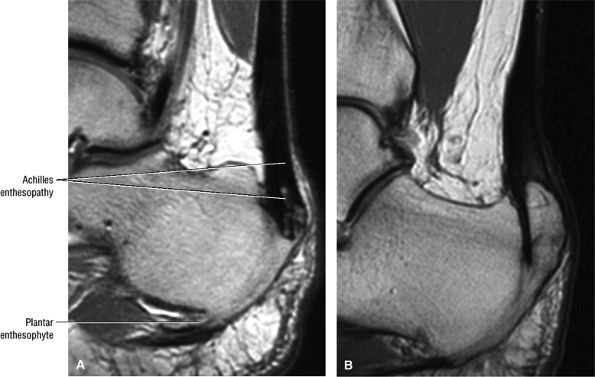

|

FIGURE 5.114 ● (A) Achilles enthesopathy or insertional tendinitis with dystrophic changes at the enthesis. A plantar enthesophyte is also demonstrated on this sagittal T1-weighted image. (B) A prominent enthesophyte and os calcis insertion tendinosis. Sagittal T1-weighted image.